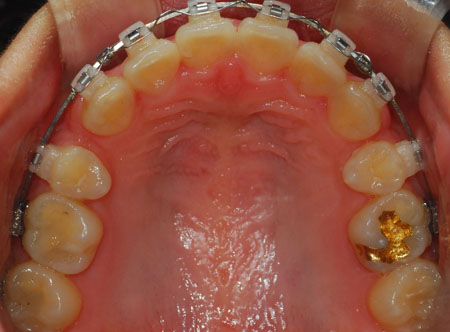

상악 사진

저기 동그라미 친 부분이 남은 발치 공간 입니다. 많이 줄어들엇죠?

노란 동그라미는 남은 발치 공간 입니다.

지금 파란 동그라미 보시면 그 공간이 거의 없습니다. 음하하하하하하핳